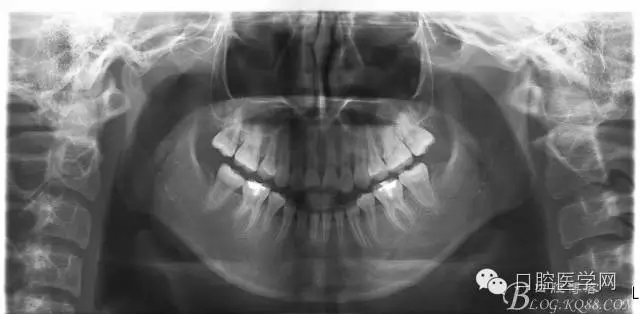

術(shù)后一個月 三個月 五個月 八個月 拔除第一雙尖牙后 曲斷片:

正畸查:替牙合。第一恒磨牙中性合。上牙弓尖圓型下牙弓方圓型。前牙覆合3度覆蓋7.5mm。下前牙咬到上舌側(cè)牙齦。上頜擁擠4.0mm,下頜擁擠

3.0mm。上頜稍前突下頜后縮,上下唇前突,上前牙覆蓋下唇,下唇外翻。面下三分之一過短,頦唇溝明顯,開唇露齒,頦饜窩明顯。顳下頜關(guān)節(jié)開閉口無彈響,無壓痛,開口型開口度正常。

2:拔牙矯治,拔出4顆第一前磨牙。

3:上下頜利用拔牙間隙解除擁擠并內(nèi)收上下前牙,改善唇側(cè)貌。

4:導(dǎo)下頜向前改善頜面?zhèn)让病?/p>